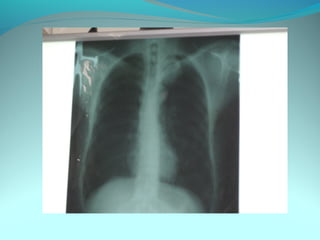

Cliché normal